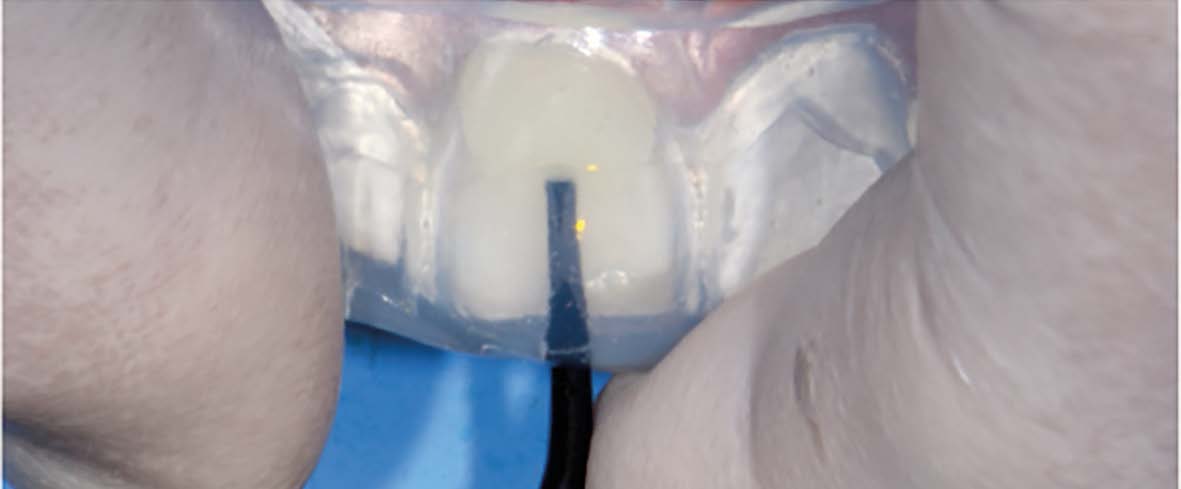

Légendes

Cas clinique n°1 - photographie 1 :

L’insertion de la clé d’injection est compatible avec la mise en place du champ opératoire.

Cas clinique n°1 - photographie 2 :

Une fois la gouttière parfaitement positionnée, l’injection peut débuter.

Elle se fait au travers du puits dédié à cet usage et débute, pour chaque dent, au niveau le plus cervical puis revient progressivement vers le bord libre en exerçant une pression continue pour prévenir la formation de bulles.